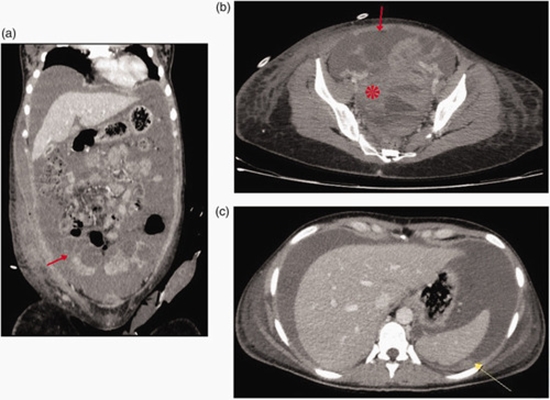

Spontaneous ovarian hyperstimulation syndrome mimicking ovarian cancer in a nonpregnant woman: A case report and literature review

Spontaneous ovarian hyperstimulation syndrome is an extremely rare condition, especially in nonpregnant women who do not exhibit exogenous ovarian stimulation. Herein, we present a case of spontaneous ovarian hyperstimulation syndrome in a 28-year-old nonpregnant woman who presented with life-threatening multiorgan dysfunction. Initial imaging studies and tumor marker assessment suggested the presence of a malignant ovarian tumor, posing substantial diagnostic challenges. The patient underwent emergency surgery due to severe hemorrhagic shock. Intraoperative findings revealed irregular and deformed ovaries; however, histologic examination showed luteinizing hemorrhagic cysts, leading to a diagnosis of spontaneous ovarian hyperstimulation syndrome. This case highlights the importance of considering spontaneous ovarian hyperstimulation syndrome in the differential diagnosis of ovarian enlargement with ascites, even in the absence of pregnancy or ovarian stimulation. It also underscores the critical role of expert radiological interpretation in such complex cases.